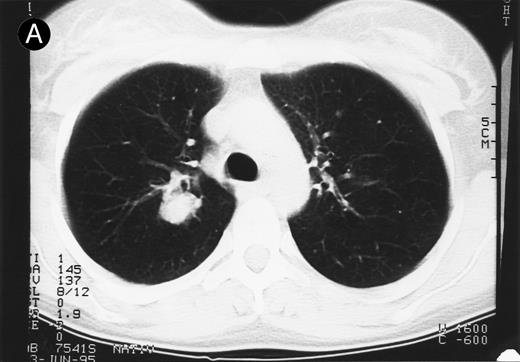

Response to therapy.In 15 of 15 evaluable patients, 1 CR and 1 PR with entire relief of B symptoms were observed after therapy with 64 mg/2 and 4 mg/m2, respectively, that lasted for 6 months and for 3 months, respectively. In addition, 3 MRs and 2 disease stabilizations (after documented preceding progressive disease) were observed, with 2 of them still ongoing after 10 and 11 months, respectively. One mixed response with a considerable reduction of a pulmonary mass (Fig 1) and left cervical lymph nodes but with growth of lymph nodes at distant sites was observed. No clear dose-response correlation could be established, although the CR occurred at the maximum dose administered (Table 2).

Response to HRS-3/A9 treatment of patient no. 7. Computed tomography (CT) scans of a pulmonary infiltration with HD in the right lung just above the tracheal bifurcation level is shown before (A) HRS-3/A9 therapy and (B) 5 weeks after the last BiMoAb infusion (4 mg/m2 × 4). The response was determined a mixed response because the partial response in the lung was accompanied by the simultaneous growth of peripheral lymph nodes.